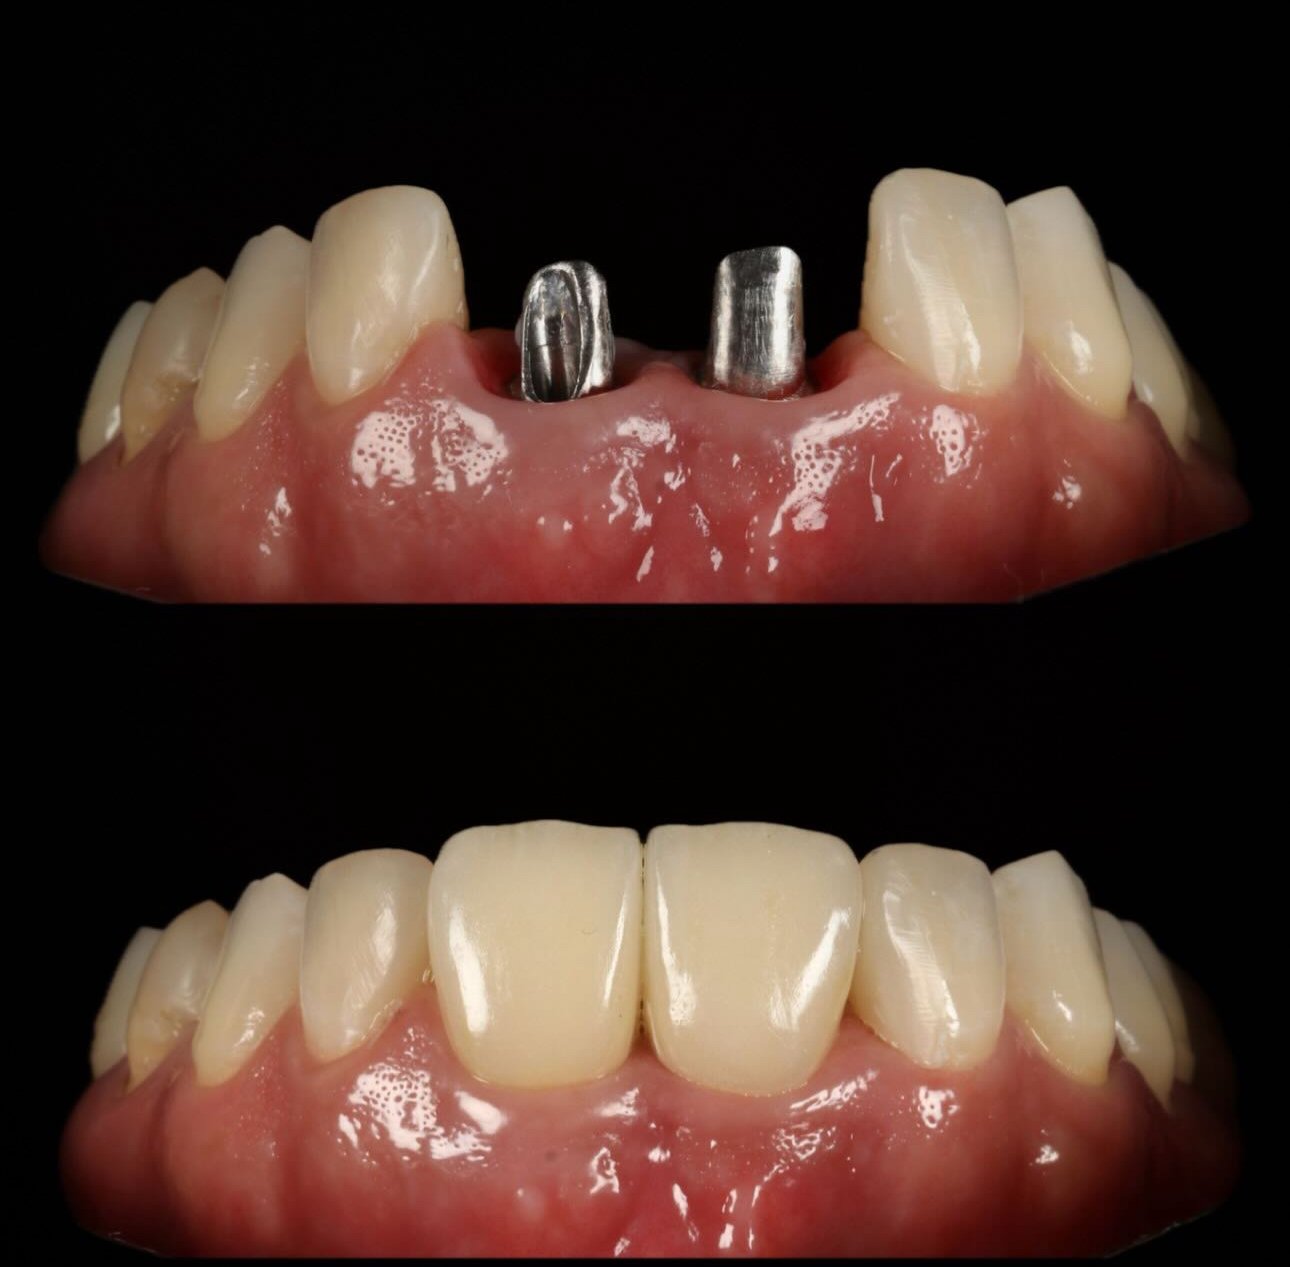

Galería de casos

Algunos resultados obtenidos en nuestra clínica.

Caso implantes 1 Caso implantes 2 Caso implantes 3 Caso implantes 4 Caso implantes 5 Caso implantes 6 Prótesis sobre implantes - Caso 7 Prótesis sobre implantes - Caso 8 Prótesis sobre implantes - Caso 9

Sí, los implantes se ven completamente naturales. Las coronas se diseñan para que coincidan perfectamente con el color, forma y tamaño de tus dientes naturales.